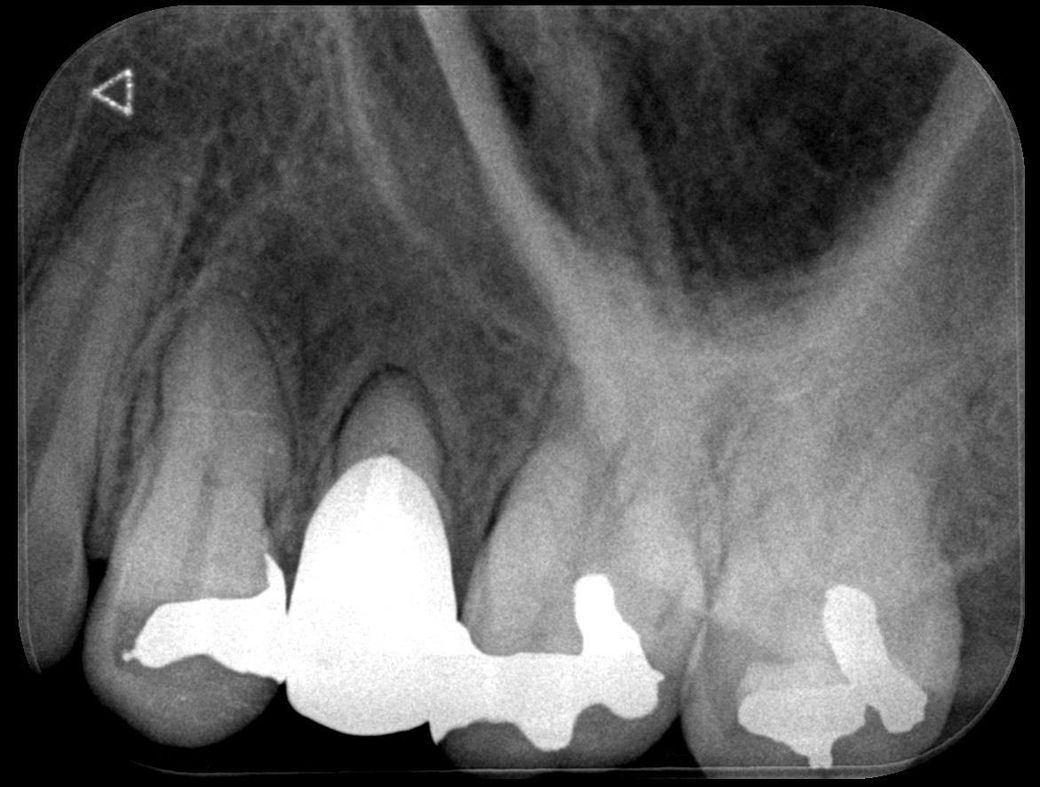

사진 찍고 진료받아보니 뿌리 쪽 잇몸 안에 큰 물혹 염증 같은 게 가득 차 있다고 크기도 많이 크고 상태가 만히 안 좋다 하셔서

이게 크라운 교체 전에는 없었는데 교체 후에 생긴 거 같다고 3년 전 사진이랑 비교해 주시면서알려주셨는데

뿌리의 병수의 크기로 보면 최근에 생긴 것이 아니라 오랜 기간 동안 진행된 것으로 보입니다. 뿌리 끝에 병소가 너무 크다면 신경치료 등으로 해결이 되지 않을 수도 있기 때문에 큰 병원에서의 치료가 필요할 수 있습니다. 자세한 확인을 위해서 치과에서 진료를 받아보세요.

뿌리끝 염증에서 비롯되는 물혹의 가능성이 있어보입니다. 현재로선 완전히 cyst화된 건 아니고 granular tissue 의 상태로 보여집니다.

발치도 염두는 해두셔야 하고 치근단절제술 등이 시도될 수는 있을 것 같습니다.